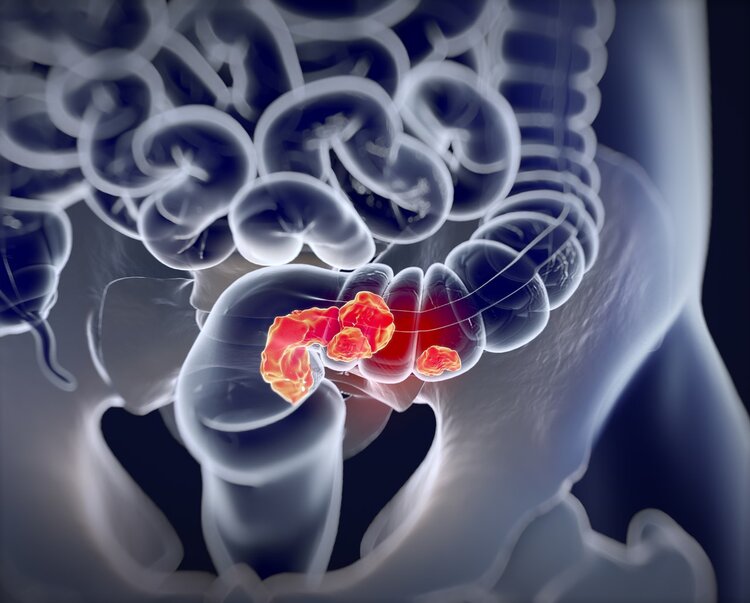

腸息肉

腸息肉

並不是所有的腸息肉都會轉變為腸癌,但腸息肉卻有可能是癌前病變,因此即使接受了手術或者腸鏡摘除也要進行複查,每隔三年還要做一次纖維結腸鏡,同時還要每年做一次糞便隱血檢查。如果患了多發性腺瘤性大腸息肉,或者息肉的直徑超過了兩釐米,在接受手術的3~6個月之內就要接受纖維結腸鏡複查,即使結果是陰性,每隔半年還要進行一次,如果一年之後腸鏡仍然沒有任何異常,那麼則可以每隔三年進行一次。

大腸腺瘤性息肉

這是常見的息肉類型,也是眾多息肉種類中癌變率較高的一種,可單發也可多發。如若患者一直未察覺息肉的存在,隨著病情不斷加重,就有可能轉化為惡性腸癌。尤其是遺傳性家族腺瘤性息肉病,癌變幾率甚至能達到100%!